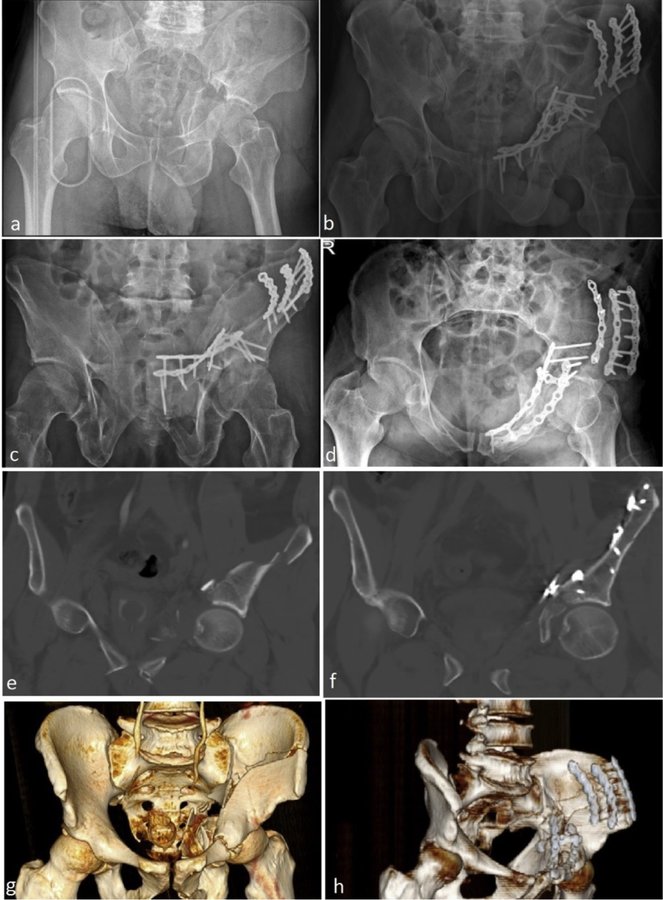

حول كاريا جراحة العظام وإعادة التأهيل عيادة كاريا جراحة العظام وإعادة التأهيل في موغلا ، تركيا تقدم رعاية العظام عالية الجودة ، بما في ذلك العلاجات الجراحية وغير الجراحية من قبل Assoc. البروفيسور الدكتور جيم يالين KILIN وفريقه. وهم متخصصون في الصدمات والإصابات الرياضية وجراحات تقويم المفاصل ، ولديهم خبرة في العلاج الطبيعي لإعادة التأهيل.